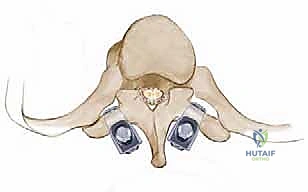

السويقات الفقارية (Pedicles): دعامة التثبيت الأساسية والمحورية

تعتبر السويقة الفقارية (Pedicle) جسرًا عظميًا أسطوانيًا يربط الأجزاء الخلفية للفقرة (القوس الفقري) بالجسم الفقري الأمامي الضخم. في جراحة دمج الفقرات الحديثة، تعتبر السويقة نقطة التثبيت الرئيسية والأقوى للمسامير المستخدمة في العملية (Pedicle Screws). يختلف شكل وحجم وزاوية السويقات بشكل كبير على طول العمود الفقري، وفهم هذه الفروق الدقيقة أمر بالغ الأهمية للجراح لضمان وضع المسامير بأمان تام وفعالية قصوى دون الإضرار بالأعصاب أو الأوعية الدموية.

2. السويقات القطنية (L1-L5):

* الحجم والشكل: أوسع بكثير وأكثر قوة وصلابة من السويقات الصدرية، مما يجعلها مثالية لتثبيت المسامير الكبيرة. يميل العرض إلى الازدياد كلما اتجهنا لأسفل (الفقرة L5 تمتلك أوسع سويقات).